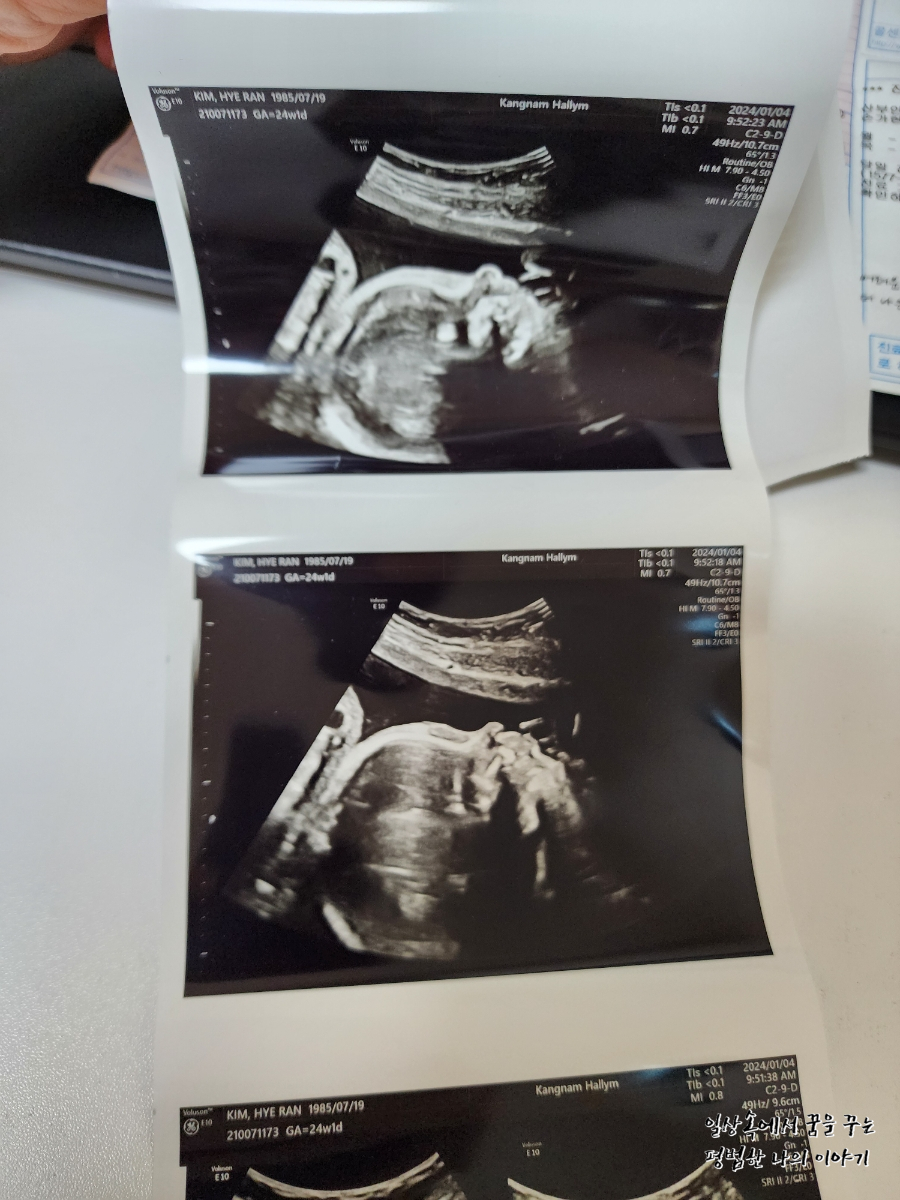

아픈 첫째 돌보면서 나도 같이 감기에 걸려 둘째를 잘 못 챙기는 게 내심 너무 미안했는데 다행히 5주 만에 만난 둘째는 건강하게 무럭무럭 잘 자라주고 있어서 얼마나 고마운지 모른다. 20주 차부터 태동이 강력하게 느껴지더니 아니나 다를까 초음파를 보는 내내 잠시도 쉬지 않고 움직인다. 첫째 때보다 태동의 정도도 강하고 횟수도 잦다. 배도 첫째때보다 빨리 나오기 시작해서 24주인 지금 트레이닝 바지 이외에는 입기가 불편하다.